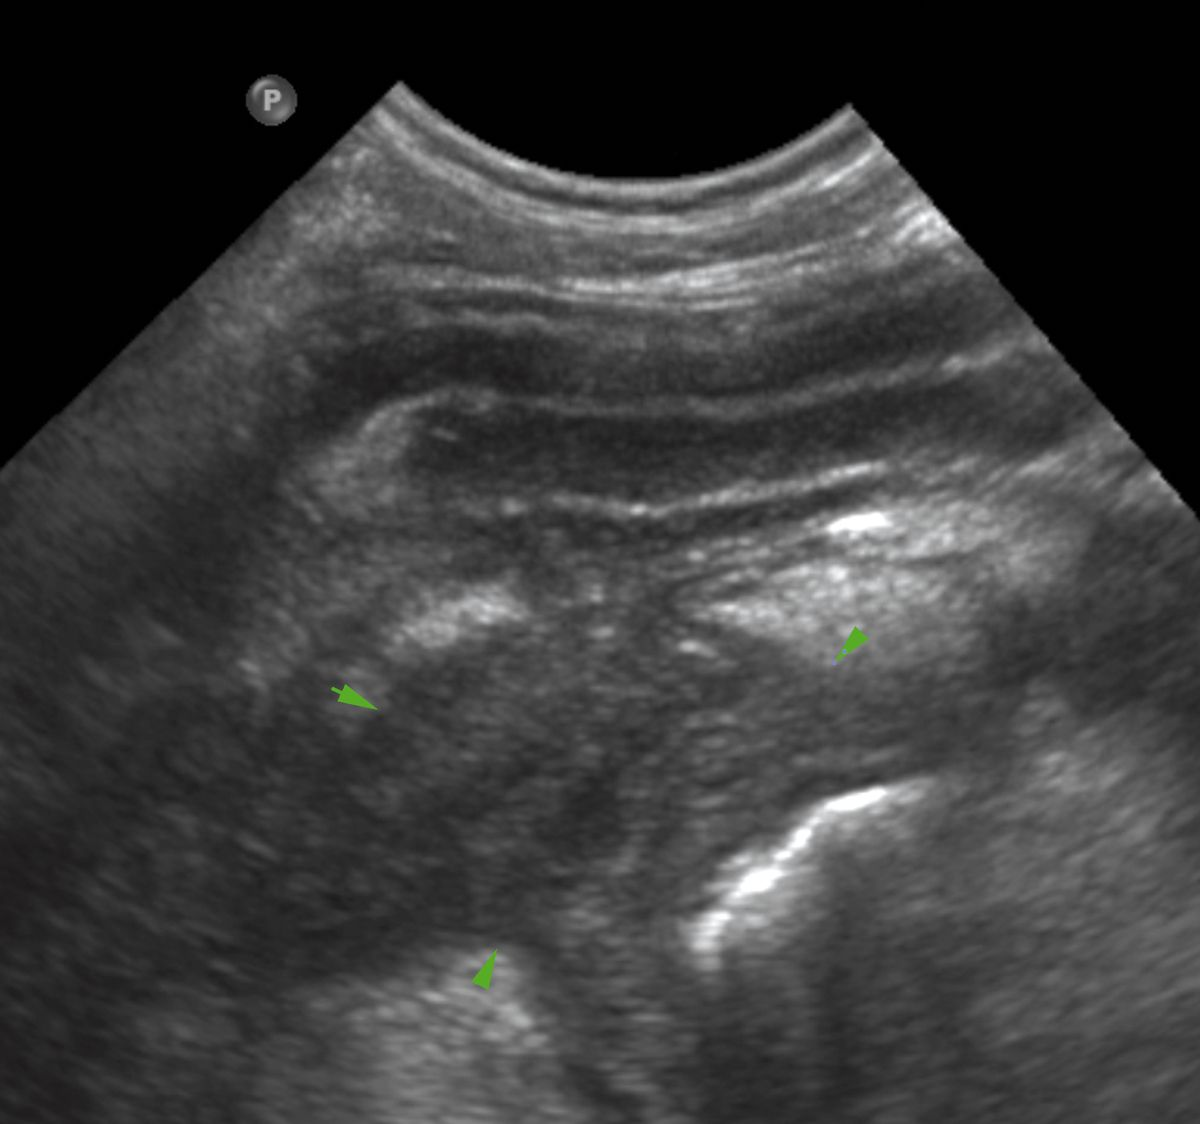

L'ecografia è utile per l'imaging del pancreas, sebbene la valutazione in modo accurato richieda una certa esperienza. Il pancreas normale è discretamente eterogeneo e di solito leggermente ipoecogeno rispetto al grasso circostante, con margini scarsamente definiti [3]. Può avere la stessa ecogenicità del grasso circostante nei gatti, e iperecogeno nello Yorkshire terrier [4]. La valutazione del pancreas si basa principalmente sull'identificazione di specifici punti di repere. Per valutare il lobo destro è importante identificare la porzione di duodeno che si estende dal rene destro, caudalmente, al piloro, cranialmente. Nel cane, la vena pancreatico-duodenale è una struttura anecogena tortuosa e tubolare facilmente identificabile, parallela alla faccia mediale del duodeno (Figura 6a); il tessuto circostante questo vaso è il pancreas. Il color Doppler può essere utile per localizzare meglio tale vaso. Nel gatto, in questa posizione si trova il dotto pancreatico, che aiuta a localizzare il lobo destro del pancreas. Il dotto pancreatico è fisiologicamente dilatato nel gatto (specialmente nei gatti anziani può arrivare fino a 3 mm di diametro) e si congiunge al dotto biliare comune a livello della papilla duodenale maggiore. Il corpo del pancreas è localizzato caudalmente rispetto al piloro e ventralmente alla vena porta, tra stomaco e colon trasverso. Il lobo pancreatico sinistro può essere visualizzato sull'aspetto laterale del colon discendente, caudalmente al fondus dello stomaco, medialmente alla milza, e cranialmente al polo craniale del rene sinistro. Anche il dotto pancreatico può aiutare a localizzare questo lobo nel gatto (Figura 6b). Nei gatti lo spessore del pancreas non deve superare il centimetro [5].

Ecografia di un pancreas normale (frecce bianche) in un cane. Il lobo pancreatico destro si trova accanto al duodeno e può essere localizzato mediante ricerca della vena pancreatico-duodenale (PDV).

Figura 6a. Ecografia di un pancreas normale (frecce bianche) in un cane. Il lobo pancreatico destro si trova accanto al duodeno e può essere localizzato mediante ricerca della vena pancreatico-duodenale (PDV).© Laurent Blond